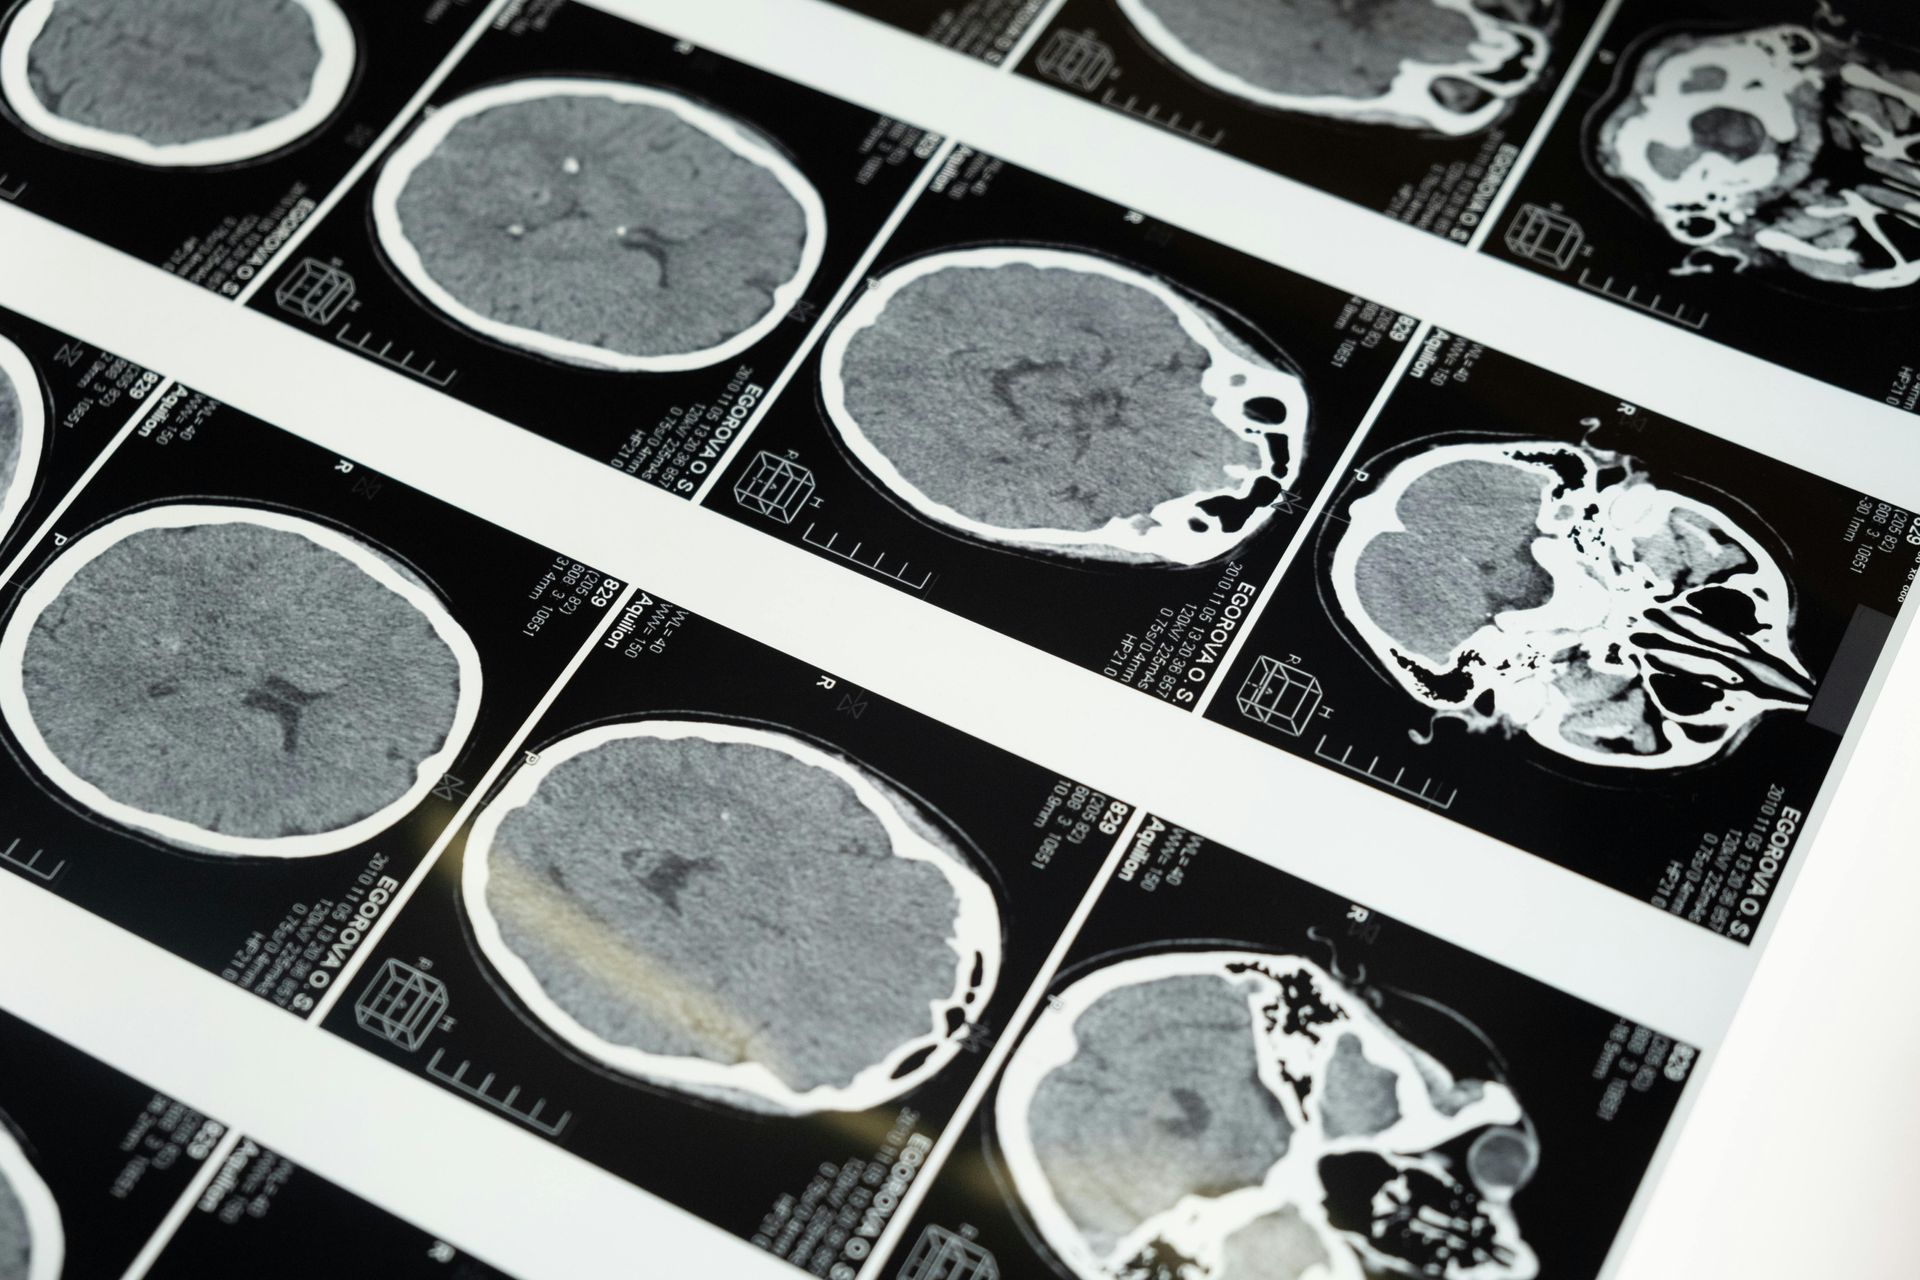

A stroke affects the brain’s ability to communicate with the body.

Stroke disrupts communication between the brain and body.

This affects how sensory input from the eyes, inner ear, muscles, and joints is processed and used to guide movement and stability. When integration is incomplete, the body adapts through compensatory patterns that limit recovery.